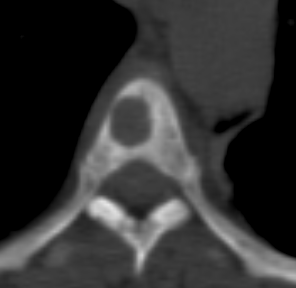

Looks like this on CT, so some concern too about compromising integrity of vert body (further)

1646424920271.png